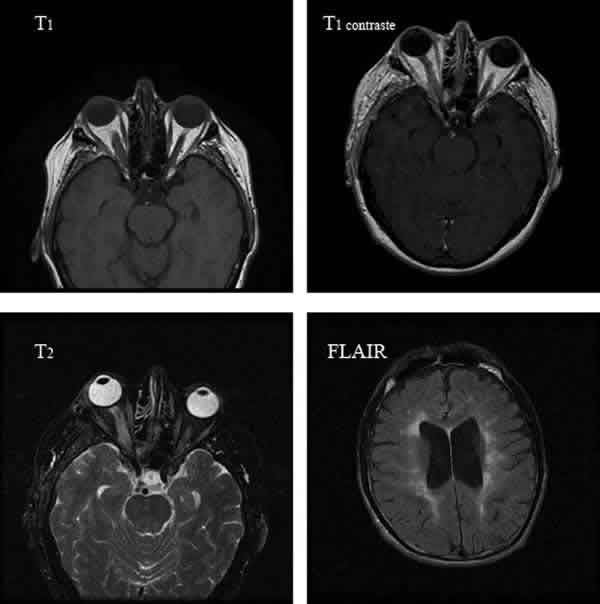

Para saber si una RM en T1 se ha realizado o no con contraste, debemos fijarnos en los vasos sanguíneos, en los plexos coroideos y en las mucosas. Si aparecen blancos, eso quiere decir que se ha utilizado gadolinio (fig. 3).

Fig. 3: En el blefarospasmo esencial no es preciso solicitar prueba de imagen,

pero el espasmo hemifacial debe solicitarse una RM, pues en raras ocasiones

puede tratarse de la primera manifestación de un tumor del ángulo

pontocerebeloso. En esta imagen se ha utilizado contraste para realzar el tumor,

como puede apreciarse los vasos sanguíneos durales aparecen brillantes.